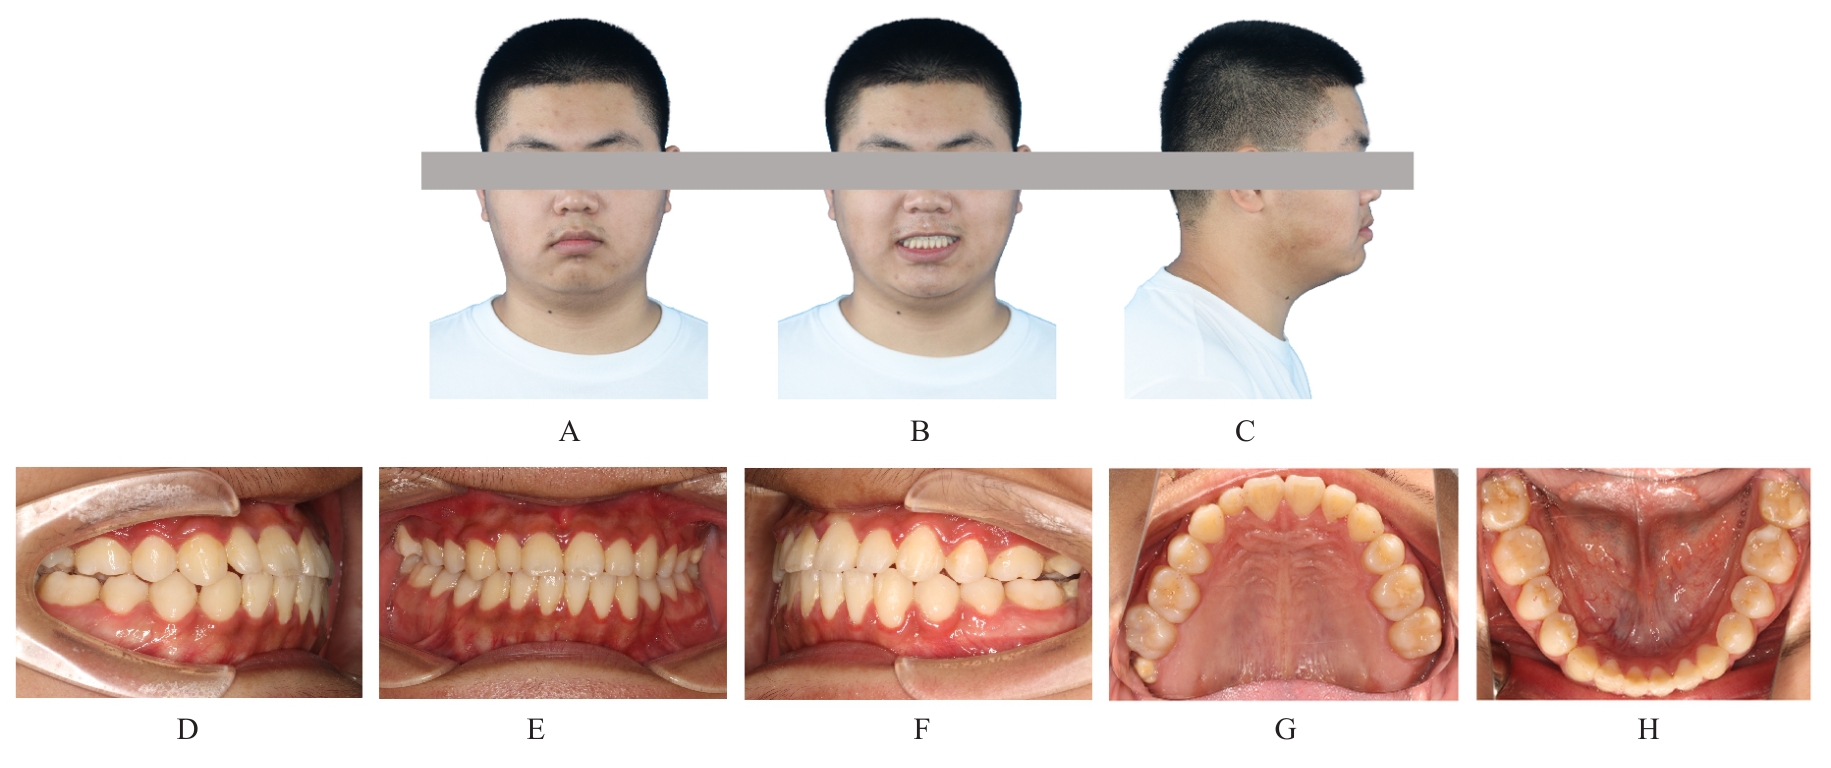

Grade Ⅲ open bite complicated with tongue hypertrophy treated by mandibular incisor extraction:A case report and literature review

Lei TIAN,Yuyan LIU,Yuqing WANG,Zhiyu ZHANG,Xiumei SUN( )

- Department of Orthodontics,Stomatology Hospital,Jilin University,Changchun 130021,China

Tab.1

Cephalometric detection analysis of patient with grade Ⅲ open bite complicated with tongue hypertrophy before and after treatment"

| Measurement | Normal (x±s) | Pretreatment | Posttreatment |

|---|---|---|---|

| SNA (°) | 82.8±4.0 | 84.1 | 83.8 |

| SNB (°) | 80.1±3.9 | 80.7 | 82.2 |

| ANB (°) | 2.7±2.0 | 3.4 | 1.6 |

| MP-SN (°) | 32.5±5.2 | 35.2 | 32.4 |

| U1-SN (°) | 105.7±6.3 | 116.9 | 111.8 |

| U1-NA (mm) | 5.1±2.4 | 6.7 | 6.6 |

| U1-NA (°) | 22.8±5.7 | 32.8 | 28.1 |

| L1-MP(°) | 92.6±7.0 | 105.7 | 93.4 |

| L1-NB (mm) | 6.7±2.1 | 8.7 | 6.8 |

| L1-NB (°) | 30.3±5.8 | 41.6 | 28.0 |

| U1-L1 (°) | 125.4±7.9 | 102.1 | 122.4 |

| Wits (mm) | -1.1±2.0 | -2.4 | -2.0 |

| APDI (°) | 86.0±4.0 | 80.8 | 85.5 |

| ODI (°) | 73.3±5.9 | 66.0 | 68.0 |

| S-Go (mm) | 80.0±4.0 | 79.7 | 82.1 |

| N-Me (mm) | 112.0±7.0 | 118.9 | 119.5 |

| S-Go/N-Me (%) | 63.0±2.0 | 67.0 | 68.7 |